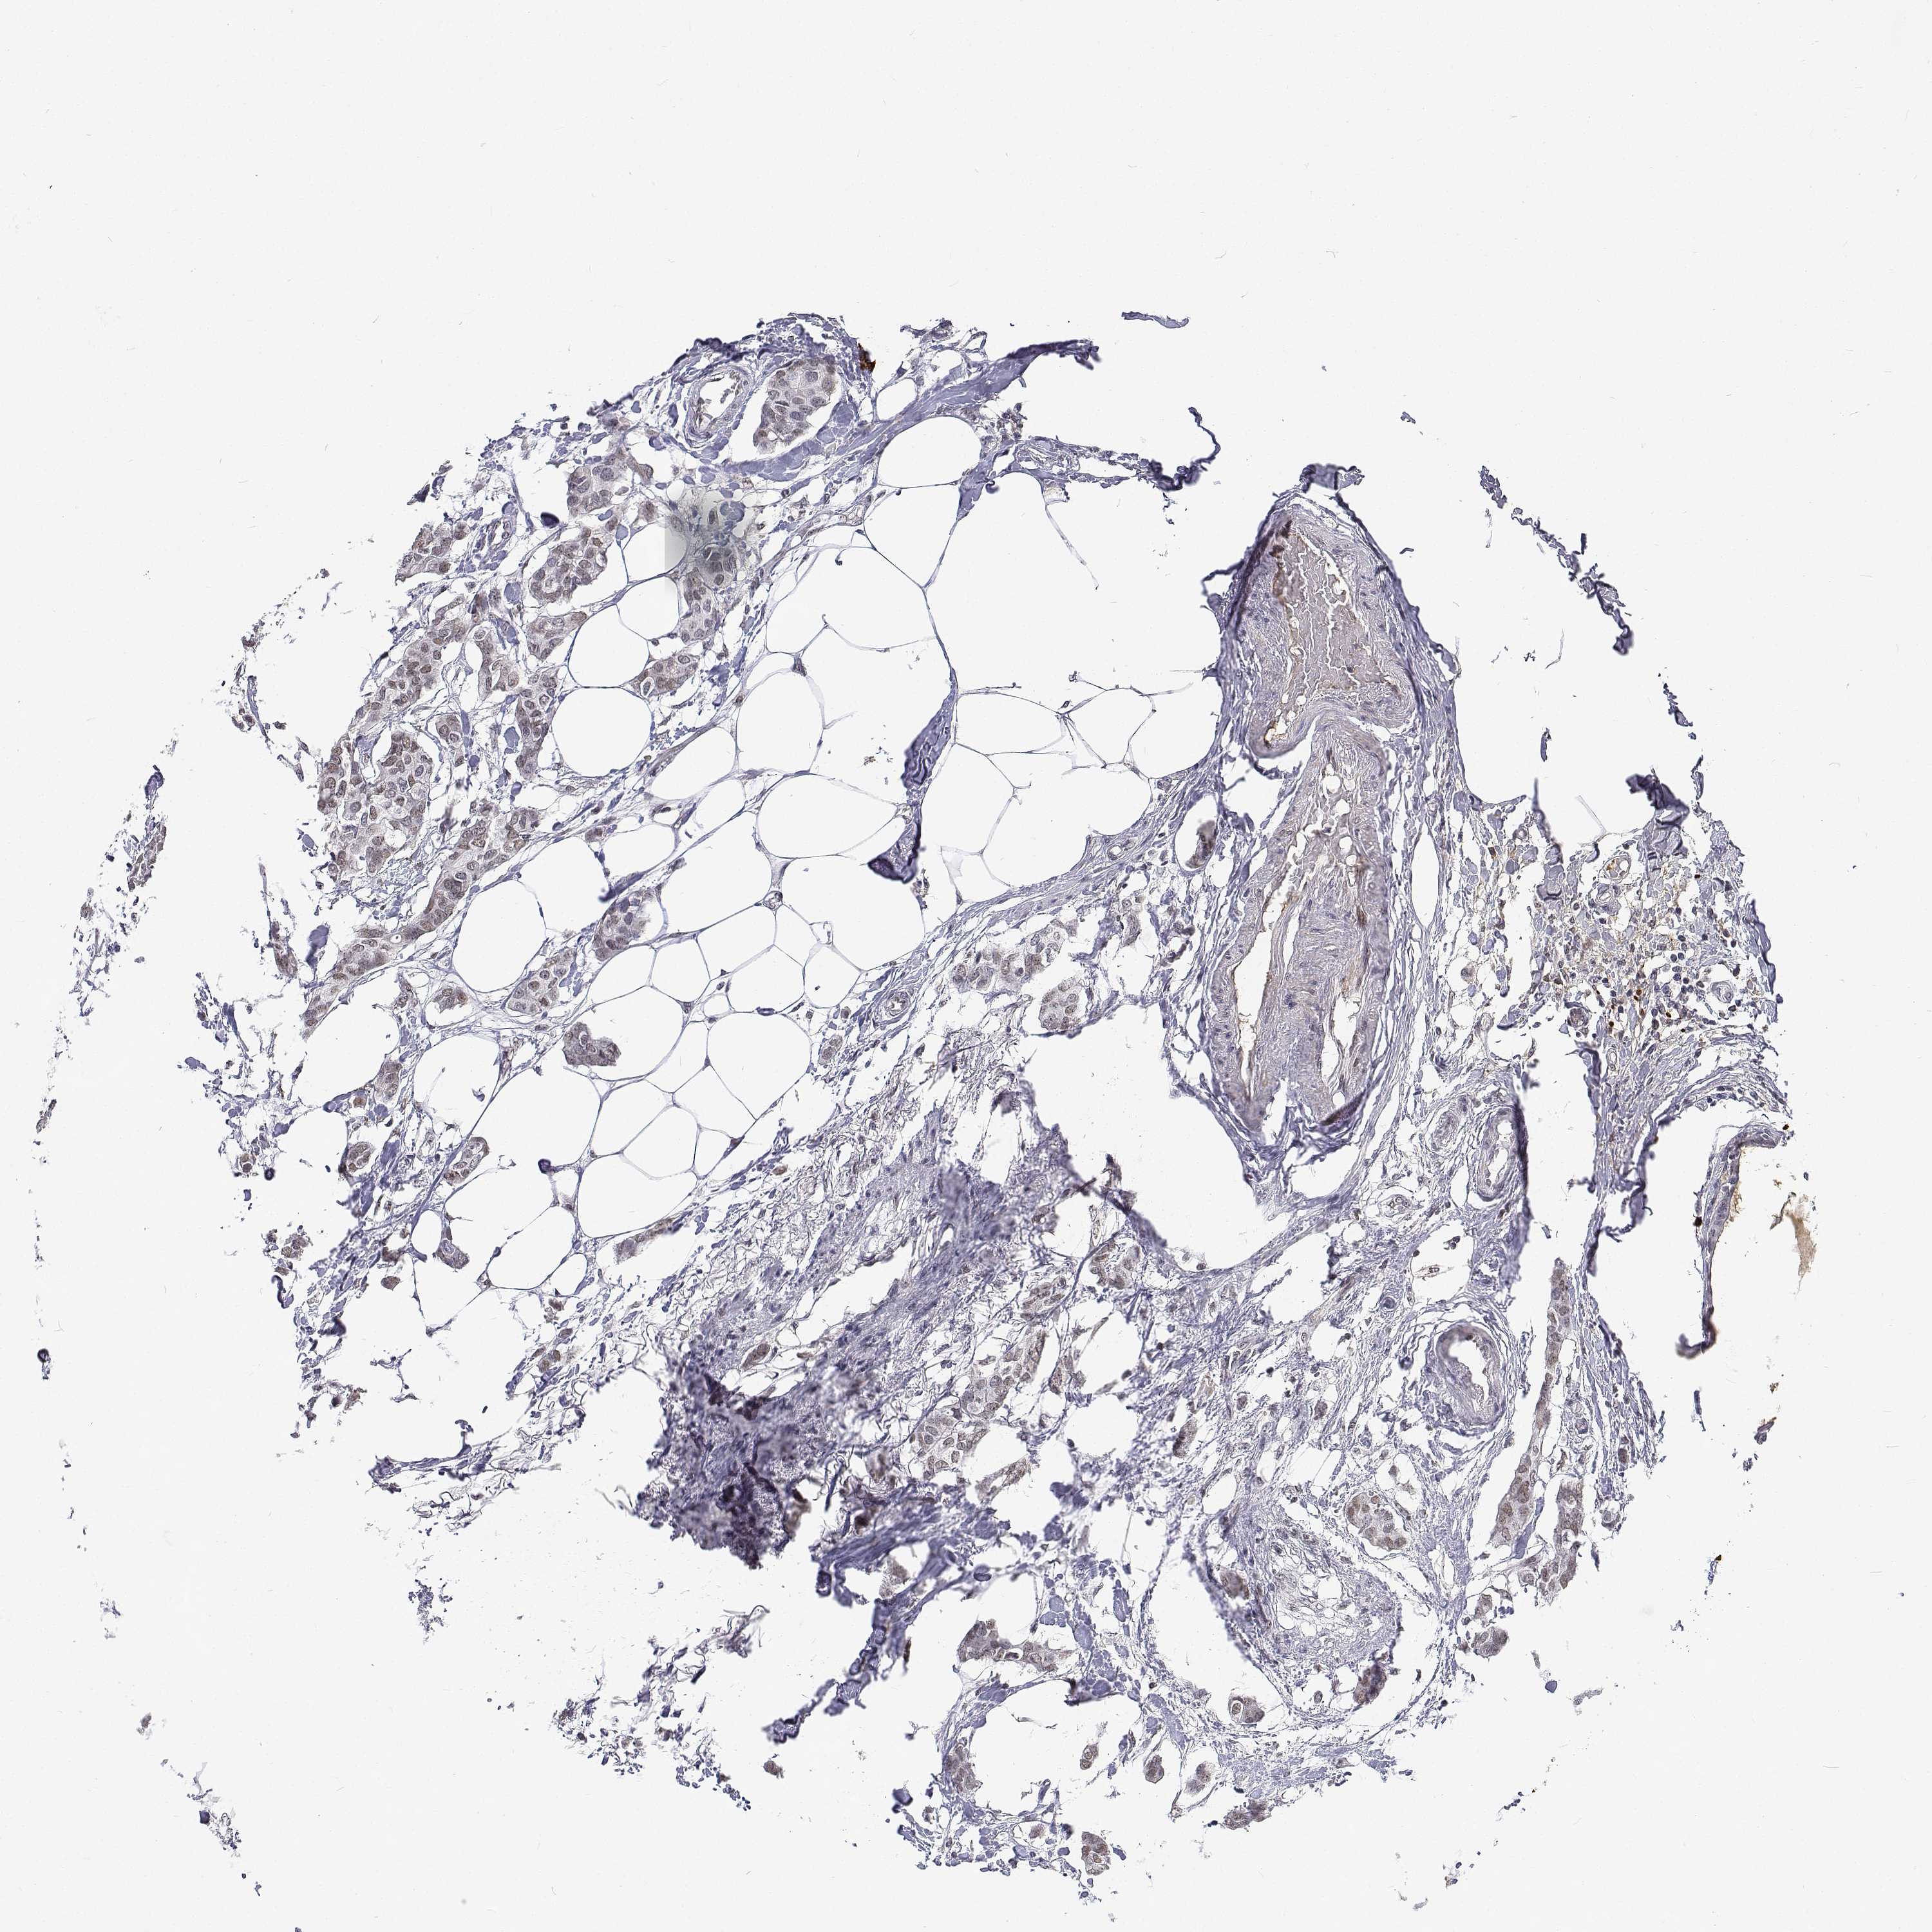

CANCER BREAST CANCER Show tissue menu

BRCA TCGA BRCA VALIDATION PROTEIN EXPRESSION

ANTIBODIES

AND

VALIDATION